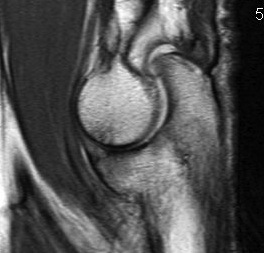

MRI

Useful in detecting early chondral damage

MRI chondral damage radiocapitella joint Chondral thinning anterior ulnohumeral joint

Chondral changes in the radiocapitellar and ulnohumeral joint